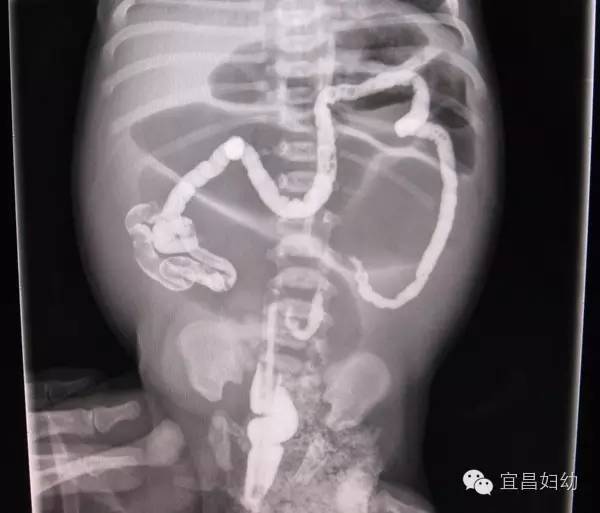

图二:先天性巨结肠钡剂灌肠。直肠、乙状结肠重度扩张,见粪渣样充盈缺损。其排空相仍见钡剂残留。

图三:先天性小肠闭锁病例。

钡剂灌肠显示细小结肠。